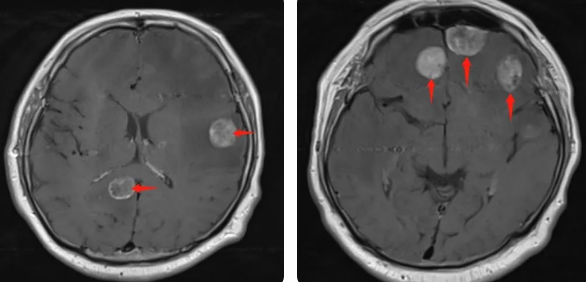

無獨有偶,60歲的左肺癌患者石先生,在外院接受了手術(shù)治療,結(jié)果術(shù)后10月出現(xiàn)腫瘤腦轉(zhuǎn)移,頭部增強MRI顯示:顱內(nèi)多發(fā)占位性病變伴水腫,接二連三的重?fù)糇屖壬霈F(xiàn)表情淡漠,沉默寡言,絕食等抑郁癥狀,VMAT放療技術(shù)與心理疏導(dǎo)雙管齊下,3周的治療后顱內(nèi)轉(zhuǎn)移病灶顯著縮小,部分甚至消失,困擾石先生的頭痛、頭暈癥狀也不復(fù)存在,石先生重拾對生活的希望,也對未來的治療充滿信心。